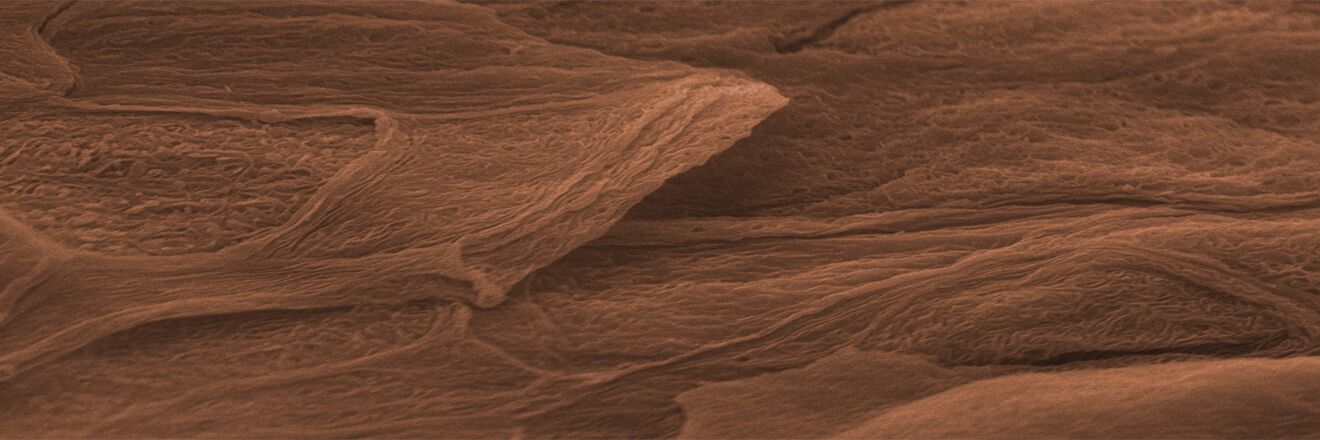

Microscopy Services setzt das patentierte Analyseverfahren Lipbarvis® (Lipid Barrier Visualisation, LBV) ein, um die epidermale Hautbarriere direkt ohne invasive Probenahmen untersuchen zu können.